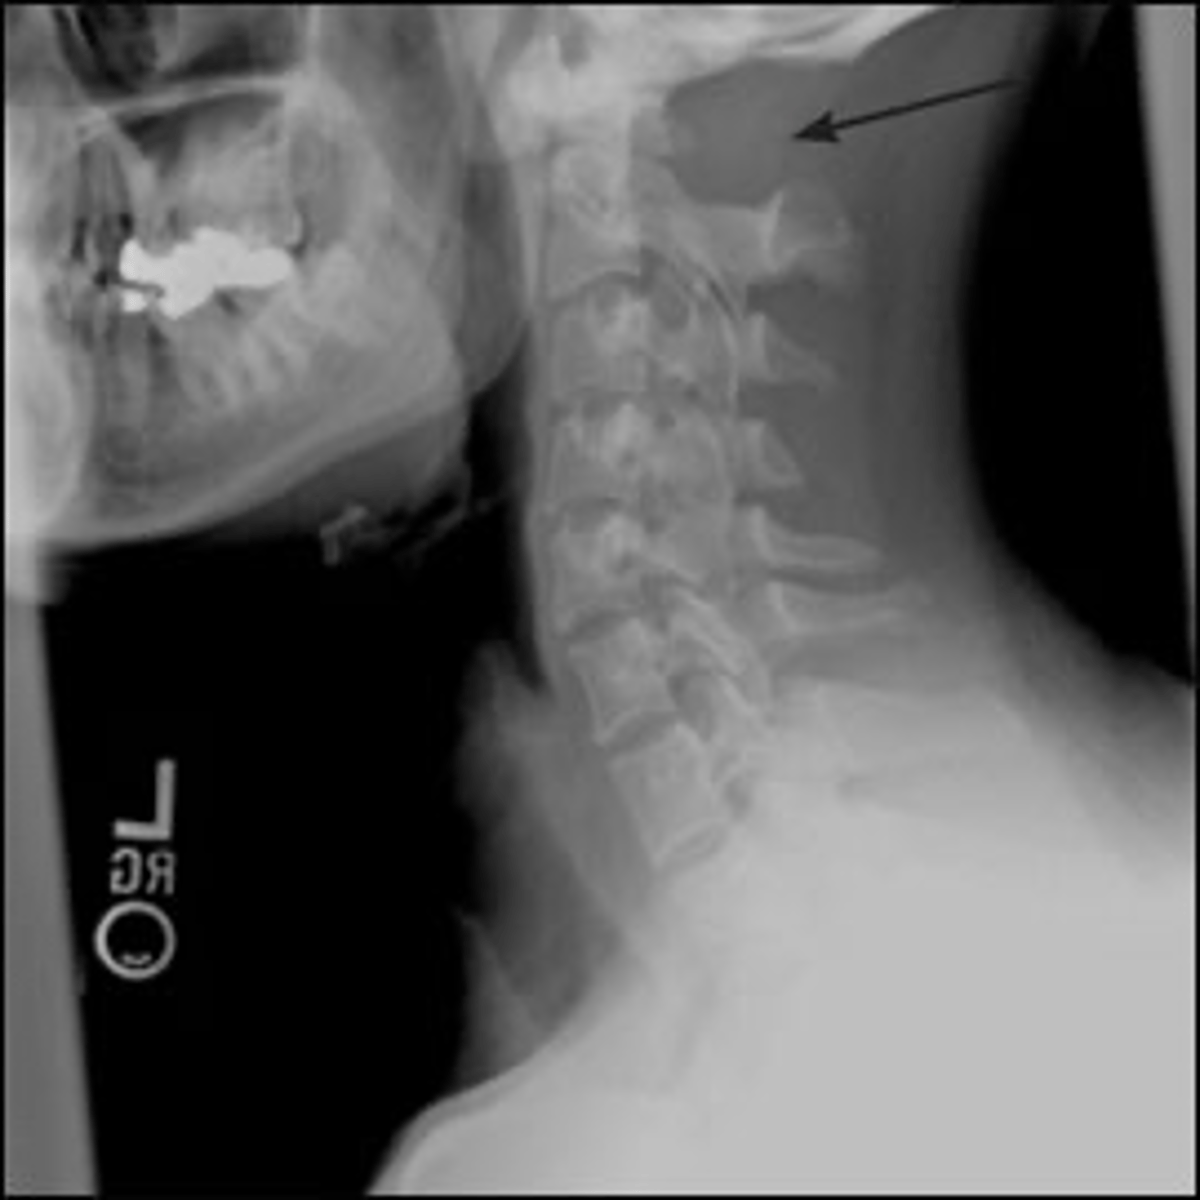

Vignette # 2

Sex: Male

Age: 23

Chief Complaint: Football player presents with nausea after being hit from behind. He reports feeling dizzy when he is stretching his neck.

1. What are your differential diagnoses? (Choose 3)

a. Dens fracture

b. Hangman's fracture

c. Os odontoideum

d. Teardrop fracture

e. Whiplash

f. Facet dislocation

g. Jefferson Burst Fracture

h. Brown Sequard

Congenital block vertebrae

Occipitalization

Atlas hyperplasia

2. What are the findings associated with this condition? (Choose 3)

a. Isthmic Spondylolisthesis

b. Spina bifida

c. Congenital block vertebrae

d. Occipitalization

e. Atlas hyperplasia

f. Hypoplastic scapula

g. Agenesis of atlas

h. Agenesis of scapula

Flexion and extension X-ray views

Neurological evaluation

CT scan

3. What other tests are most likely to be performed to evaluate this condition?

(Choose 3)

a. Flexion and extension X-ray views

b. Orthopedic evaluation

c. Neurological evaluation

d. Bone scan

e. CT scan